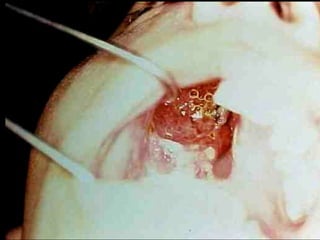

Eliminación de focos sépticos en bloque en paciente con osteitis

mandibular crónica

Osteitis

Imagen microscópica de osteitis, inicialmente existe una etapa de

osteoclastosis seguida por regeneración. No siempre el hueso

regenera en su totalidad y sigue el curso de cualquier inflamación

dejando un area de tejido fibroso que con el tiempo puede

calcificarse (hueso denso)

Manejo con antibióticos obligado

Revisión periódica